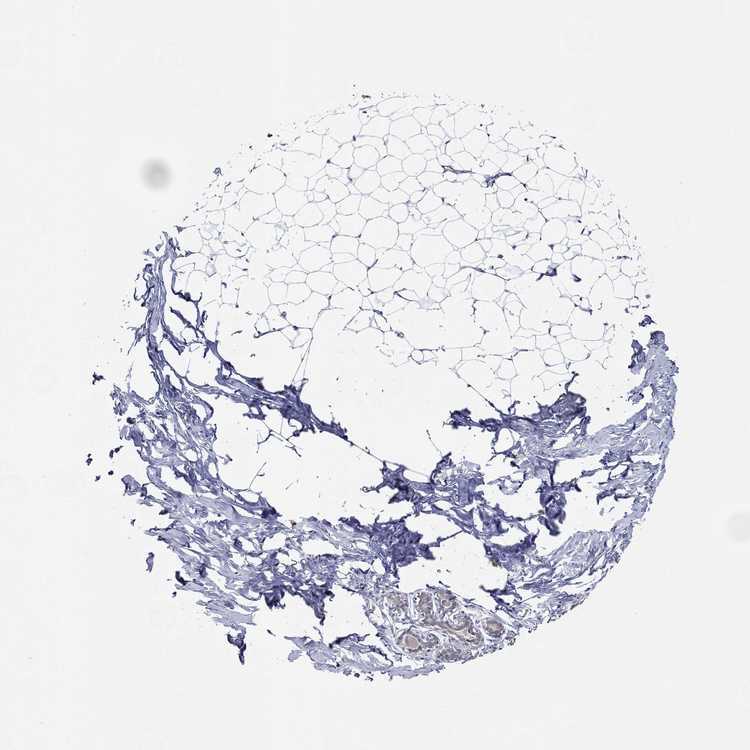

BREAST - Antibody stainingi

Antibody staining in the annotated cell types in the current human tissue is reported as not detected, low, medium, or high, based on conventional immunohistochemistry profiling in selected tissues. This score is based on the combination of the staining intensity and fraction of stained cells.

Each image is clickable and will lead to virtual microscopy that enables deeper exploration of all samples and also displays staining intensity scores, fraction scores and subcellular localization as well as patient and tissue information for each sample.

Antibody HPA068443

Adipocytes Not detected

Glandular cells Medium

Myoepithelial cells Not detected